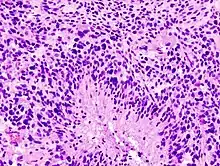

Glioblastomas are characterized by the presence of small areas of necrotizing tissue that are surrounded by anaplastic cells. This characteristic, as well as the presence of hyperplastic blood vessels, differentiates the tumor from grade 3 astrocytomas, which do not have these features.